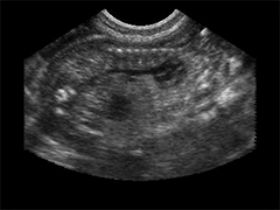

עוד עובר מקסים בן 6 שבועות